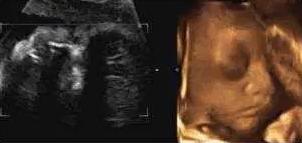

【在妇产科医院,你可以看到这样的胎宝】

本宝宝有些乏了——揉眼睛